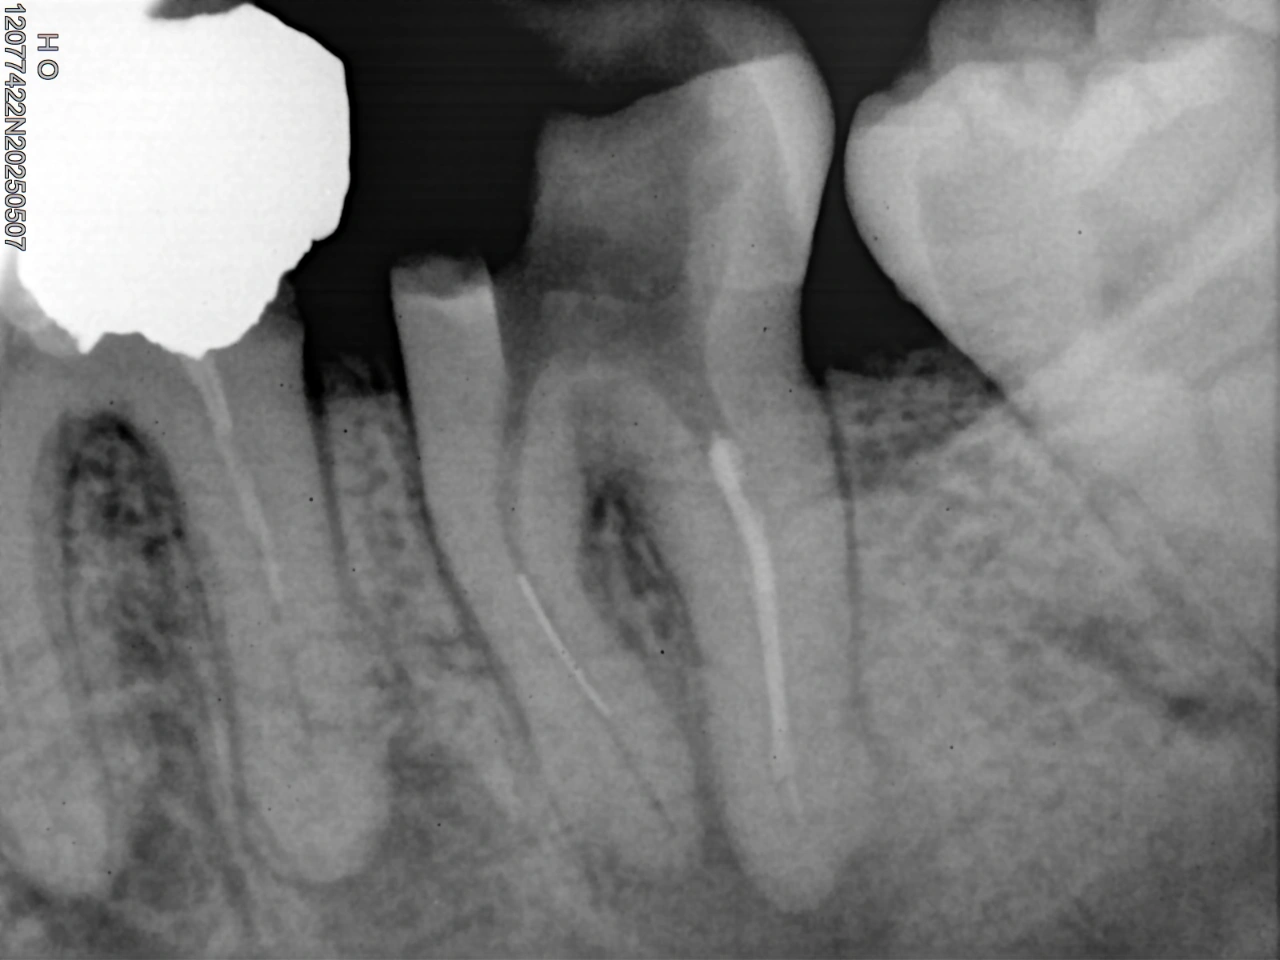

Clinical Cases